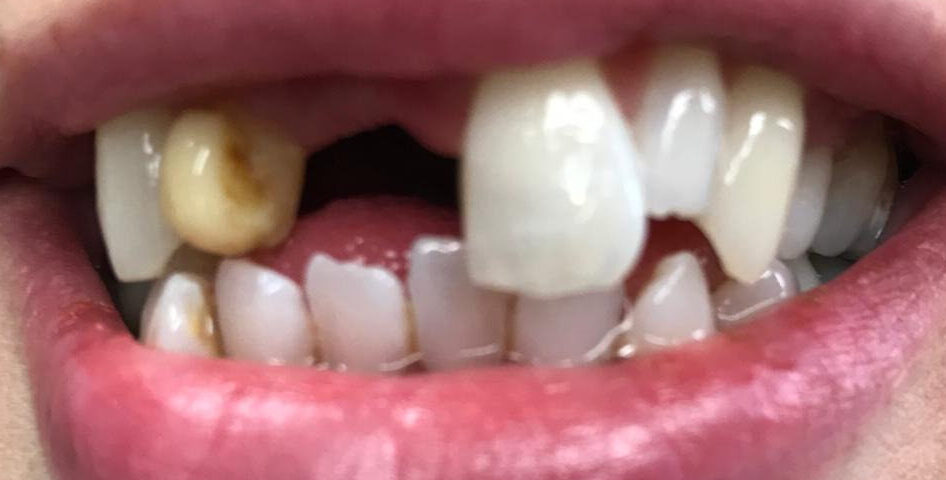

Incisor Implant

Missing front incisor

Before

After